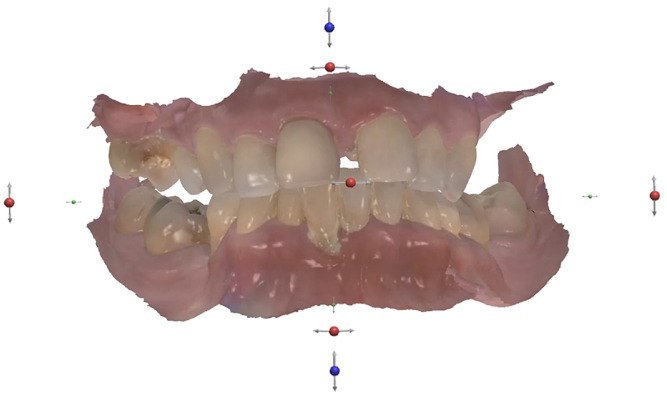

Fig. 3

In accordance with the radiographic and clinical evaluation, the patient case was classified as surgically and prosthodontically complex in terms of the International Team for Implantology’s SAC classification (Fig. 3). The SAC classification aids in assessing the degree of difficulty and risk associated with implant-related rehabilitation.